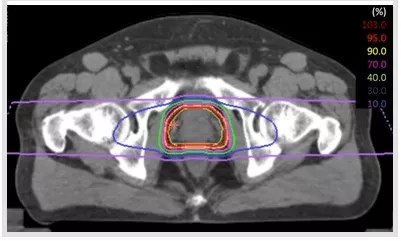

但是傳統(tǒng)的光子放療會導(dǎo)致直腸和膀胱不良事件的產(chǎn)生,不利于前列腺癌患者生活質(zhì)量的提升。與傳統(tǒng)的光子放療不同,質(zhì)子治療及重離子治療這兩種新興的放療手段在人體內(nèi)會產(chǎn)生“布拉格峰效應(yīng)”,簡單說就是進入人體時能量小,達到腫瘤處能量突然暴增,因此對正常組織損傷非常小。相比傳統(tǒng)的光子放療,質(zhì)子重離子治療前列腺癌的效果更加顯著,且減少了膀胱、直腸和陰莖球的輻射劑量,副作用更低。

在日本QST醫(yī)院與日本國內(nèi)其他重離子治療設(shè)施的多設(shè)施回顧性試驗中,經(jīng)重離子治療后低危前列腺癌的5年生存率為100%,中危前列腺癌5年生存率為99%,高危前列腺癌為96%,且5年出現(xiàn)重度并發(fā)癥的概率為0[4],效果可與外科手術(shù)相媲美(根據(jù)《中國前列腺癌診治指南2018》中的數(shù)據(jù),低危前列腺癌根治術(shù)后死亡率為5%[5])。

▲重離子治療前列腺癌|圖源:日本QST醫(yī)院